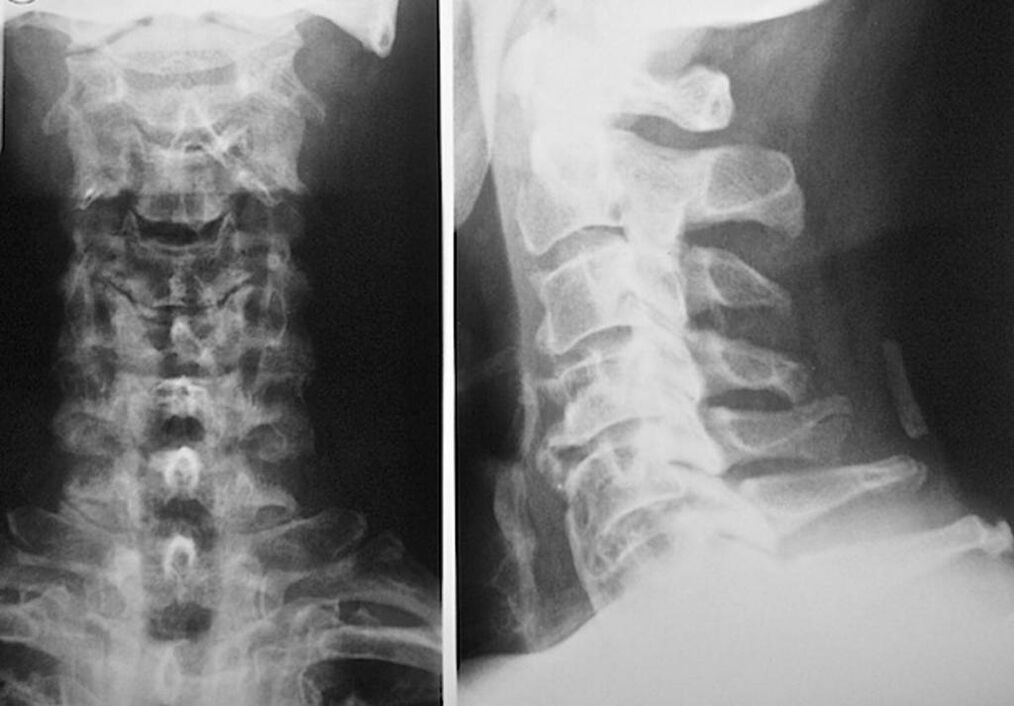

Za diagnozo in natančno oceno stanja medvretenčnih ploščic se uporabljajo naslednje raziskovalne metode:

- Radiografija.

- Pregled z računalniško tomografijo.

- Magnetna tomografija.

- Ultrazvočno skeniranje vratnih žil.

Vsak od njih je popolnoma varen za zdravje in ne predstavlja nevarnosti prekomerne izpostavljenosti. Diagnoza osteohondroze vratnih vretenc, katere zdravljenje se bo izvajalo do konca življenja, se lahko izvede po preprostem vizualnem pregledu. Vsak ortoped to zlahka naredi. Izjema je prva stopnja bolezni, ko ni opaziti vidnih patologij v predelu materničnega vratu.